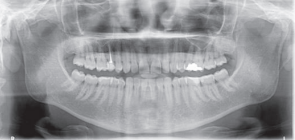

患者38岁,女,发现牙龈无痛性增生肿胀。患者未服用任何药物,未处于妊娠期,家族史无异常。

口内检查发现患者13、14牙间牙龈肿胀,质硬,无蒂,牙龈周围轻度菌斑堆积,牙龈轻度红肿。13、14牙不松动。